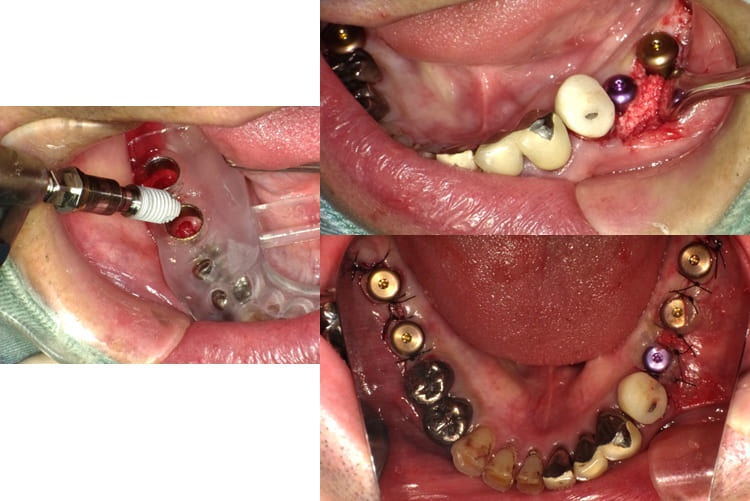

治療

上顎前歯部と小臼歯部の温存不可能な残根を抜歯して1か月ほど待機して歯肉が抜歯窩を完全に閉鎖した状態でCTと口腔内の印象を取り最終補綴の予想WAX UPを1行いサージカルガイドを作成した。その後、上顎にインプラント8本を埋入した。

上顎にインプラント8本を埋入した術後のパノラマXP所見:上顎骨に対するインプラントの長さに関しては12mm-10mmが適切であり前歯部では12mmを小臼歯部では10mmを選択している。また左下のブリッジに関しては温存できなかった第2大臼歯が抜去されている。

上顎のインプラント埋入後約1か月で、両側下顎臼歯部にインプラント埋入を行った。左下のインプラント埋入では小規模の骨増生を伴うインプラント埋入を行った。

両側下顎臼歯部に対してのインプラントについては8mmから10mmが選択されるが骨量が十分あったことから10mmを選択して埋入した。左側の小臼歯部では水平的骨が若干、不足しているためドリリング時に採取された自家骨を骨増生として利用した。

上顎前歯部と両側小臼歯部はインプラント補綴を行い、両側の大臼歯部についても根管治療からやり直して咬合平面を改善すべく補綴を行った。下顎の両側臼歯部に関してもインプラント補綴を行い小臼歯部では根管治療からクラウンによる補綴を行った。左上7番に関しては当初インプラント補綴を行う予定であったがサイナスリフトを伴う治療になることと第一大臼歯までで十分噛めることから埋入せずに経過を見ている。

治療後の口腔内所見である噛み合わせも問題なく機能している。また、一本ずつのインプラント補綴を行ったことでフロスによるケアができ良好な口腔内環境を維持できている。